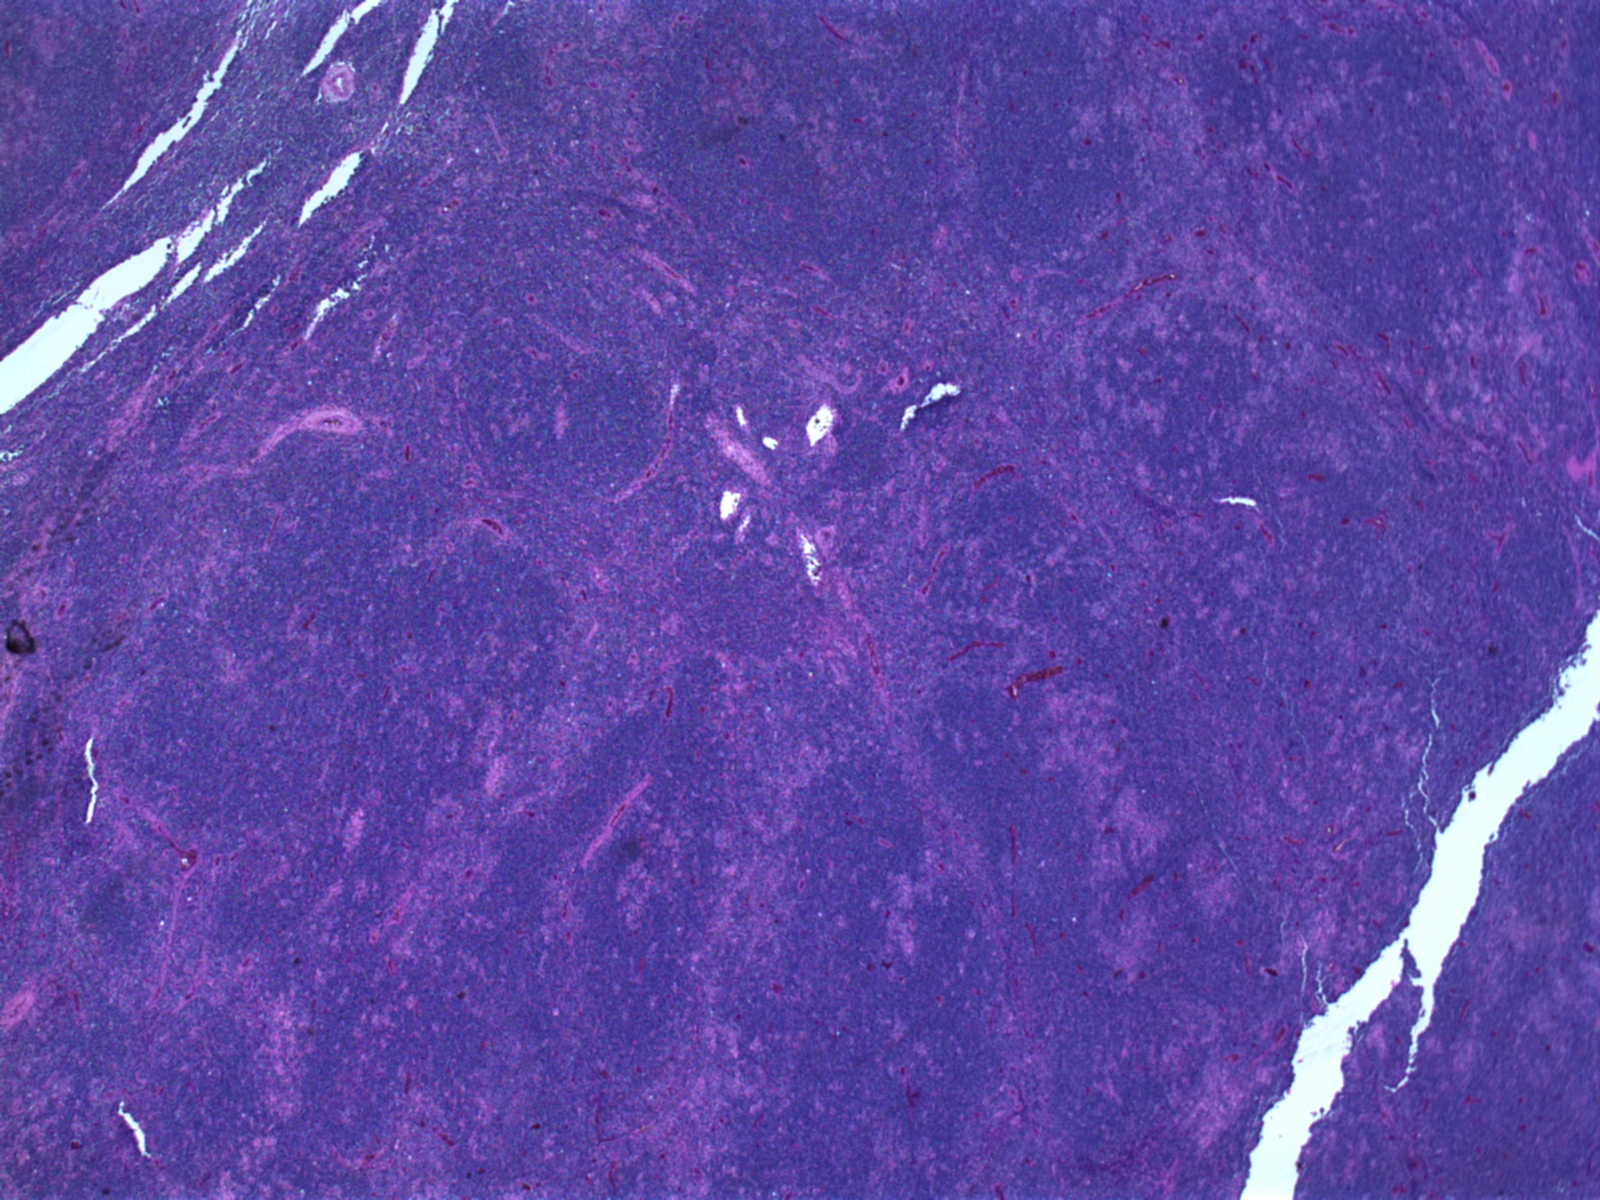

림프종은 림프절 생검을 통해 확실하게 진단된다.[167][22] 생검은 현미경 검사를 위해 림프절을 부분적으로 또는 전체적으로 절제하는 것을 의미하며, 이 검사를 통해 림프종을 나타낼 수 있는 조직병리학적 특징을 확인할 수 있다.

림프종이 의심되는 경우 초기 평가로 절제된 림프 조직을 유리 슬라이드에 가볍게 눌러 염색(보통 H&E 염색)한 후 광학 현미경으로 관찰하는 "터치 프렙(touch prep)" 과정을 거치기도 한다.